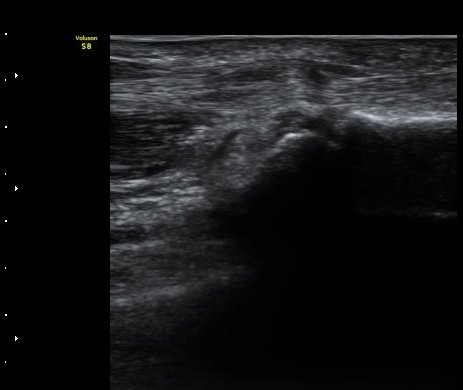

ÃÊÀ½ÆÄ °Ë»ç

ÈûÁÙÀÇ Á¾´Ü¸é°Ë»ç¿¡¼­ A1 ȰÂ÷(pulley)ÀÇ Àú¿¡ÄÚ ºÎÁ¾°ú ȰÀÚ ±ÙÀ§ºÎ¿¡¼­ ÈûÁÙÀÇ

ºÎÁ¾ÀÌ °üÂûµÊ(±×¸² 1, 2). ÈûÁ٠Ⱦ´Ü¸é°Ë»ç¿¡¼­ A1ȰÂ÷ÀÇ Àú¿¡ÄÚ ºÎÁ¾ÀÌ °üÃÔµÊ(±×¸² 3).